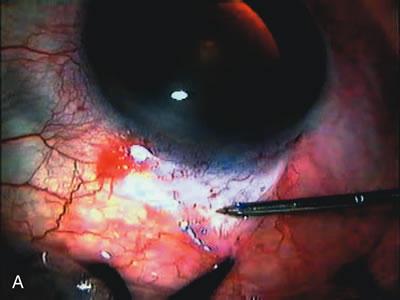

Fig. 8. Bleb appearance after limbus-based versus fornix-based conjunctival flaps. Even though the IOP is thought to be equivalent between limbus and fornix-based conjunctival flaps, the final bleb appearance varies considerably. A. During a limbus-based approach, an incision through conjunctiva 10 mm posterior to limbus will sever through multiple arterial vessels, increasing the likelihood of an avascular bleb. B. The tissues are dissected down to the sclera further cutting feeder vessels from Tenon's capsule. C. The wound is closed inciting a cascade of wound healing events that may ultimately lead to scarring producing a barrier to aqueous flow. D. This leads to walling off of a bleb that has lost some of its overlying vascularity (pale cystic avascular bleb). E. During a fornix-based conjunctival approach, the incision is made at the limbus and tissues undermined. F. The incision is closed at the limbus; no conjunctival vessels are severed over the bleb area. G. This fosters the formation of a shallow diffuse pale bleb with a normal vessel pattern.

During preoperative slit-lamp biomicroscopy, the surgeon evaluates the condition of the conjunctiva and decides on a fornix-based or a limbus-based conjunctival approach.174–177 There are definite advantages and disadvantages of each approach (Table 3). With proper wound construction, there appears to be very little difference in long-term IOP control between the two incisional groups. However, the long-term bleb appearance varies considerably between the two incisional groups,178 with a limbus-based conjunctival flap more likely to develop a cystic bleb especially if an antimetabolite is used179 (Fig. 8).